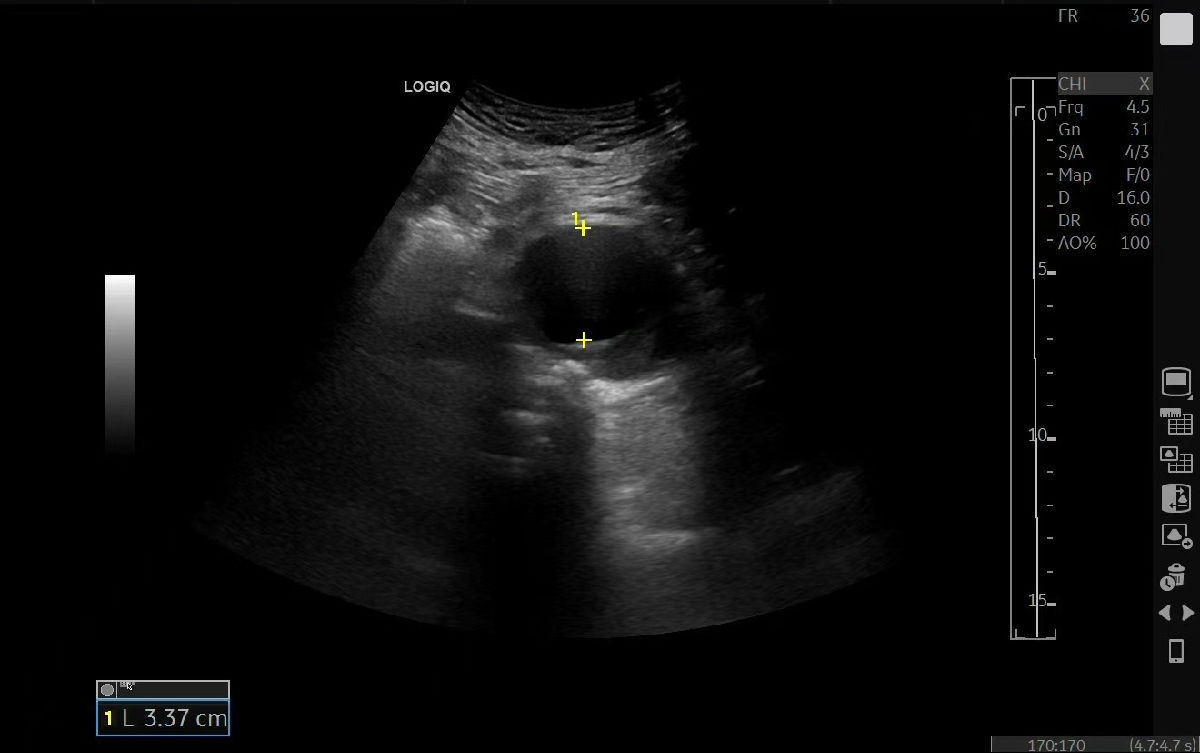

该患者因不明原因身体不适来我院就诊,超声医学科成为探查病情的“第一关”。腹主动脉夹层动脉瘤起病隐匿、进展凶险,诊断难度极高。科室团队凭借扎实的技术与丰富的经验,在细致检查中敏锐捕捉到可疑征象。为谨慎起见,医院迅速启动多学科会诊(MDT),超声医学科与医学影像科专家共同研判、交叉验证,最终明确诊断为腹主动脉夹层动脉瘤,为后续治疗争取了宝贵的“黄金时间”。

“此类疾病的救治,关键在于早发现、准判断。”超声医学科主任赵君智主任医师指出。超声以其无创、便捷、实时成像的优势,成为该病筛查与初诊的重要工具。此次精准诊断不仅为治疗提供了关键依据,也为后续向华西医院转诊搭建了扎实的沟通基础。鉴于病情复杂危重,我院在完成全面评估与稳定病情后,积极协助患者转至国内顶尖的四川大学华西医院进一步治疗。

此次患者返回我院超声医学科复查,超声显示支架位置精准、血流通畅,恢复情况理想。“当时真的非常害怕,多亏咱超声医学科的医生精准细致的检查,华西医院的专家又妙手解难,我才重获健康!”患者紧紧握住科室医护人员的手,激动地表示感谢。